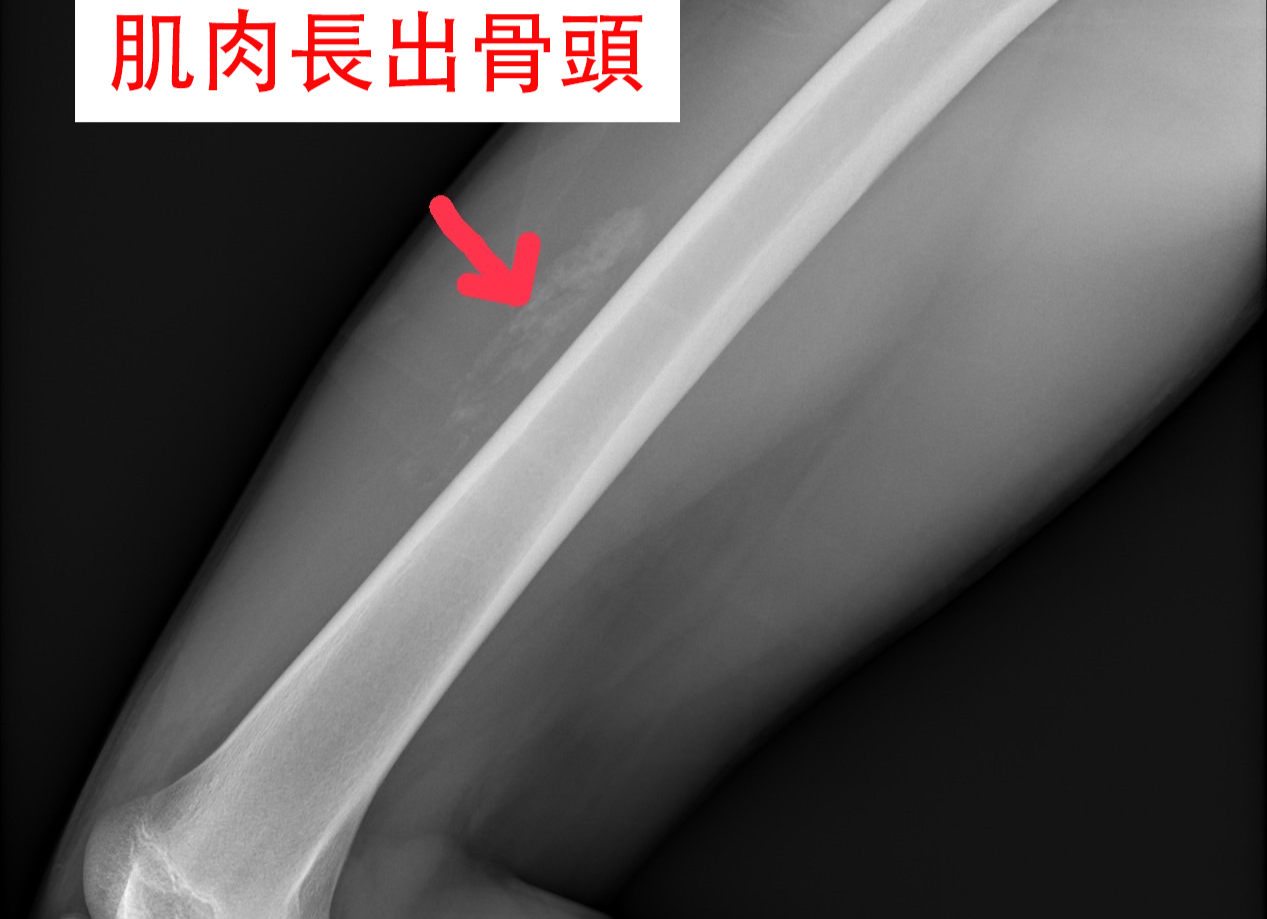

「股四頭肌肌肉挫傷」,是籃球運動中常見的身體碰撞所導致的運動傷害,從輕微的腫脹、痙攣、皮下瘀血到嚴重的肌肉撕裂傷及血腫都有可能。1週後的門診追蹤,股四頭肌的肌肉裡居然長出了「骨頭」,就是醫學上的「骨化性肌炎」。 復健科何宇淳醫師表示,肌肉挫傷是常見的運動傷害,但是骨化性肌炎就比較少見,它比較容易發生在15到30歲的年輕人,這種特殊的情況是因為肌肉受傷後,間質細胞過度活躍,分化形成了鈣化性組織,也就是骨頭的生成。

復健科何宇淳醫師指出,「骨化性肌炎」可以服用非類固醇消炎藥,降低受傷組織的發炎性反應及緩解症狀,輔以物理治療的冷熱交替療法及關節運動,來消除腫脹及維持肌肉的彈性。復健科何宇淳醫師特別強調,避免讓受傷的肌肉過度的刺激,不可以去做推拿,因為可能會讓骨化的情形變嚴重。骨化性肌炎需要頻繁的門診超音波追蹤,有些人的骨化會慢慢地吸收消失,有些人的骨化,若是影響到關節活動,就需要考慮手術的治療了。